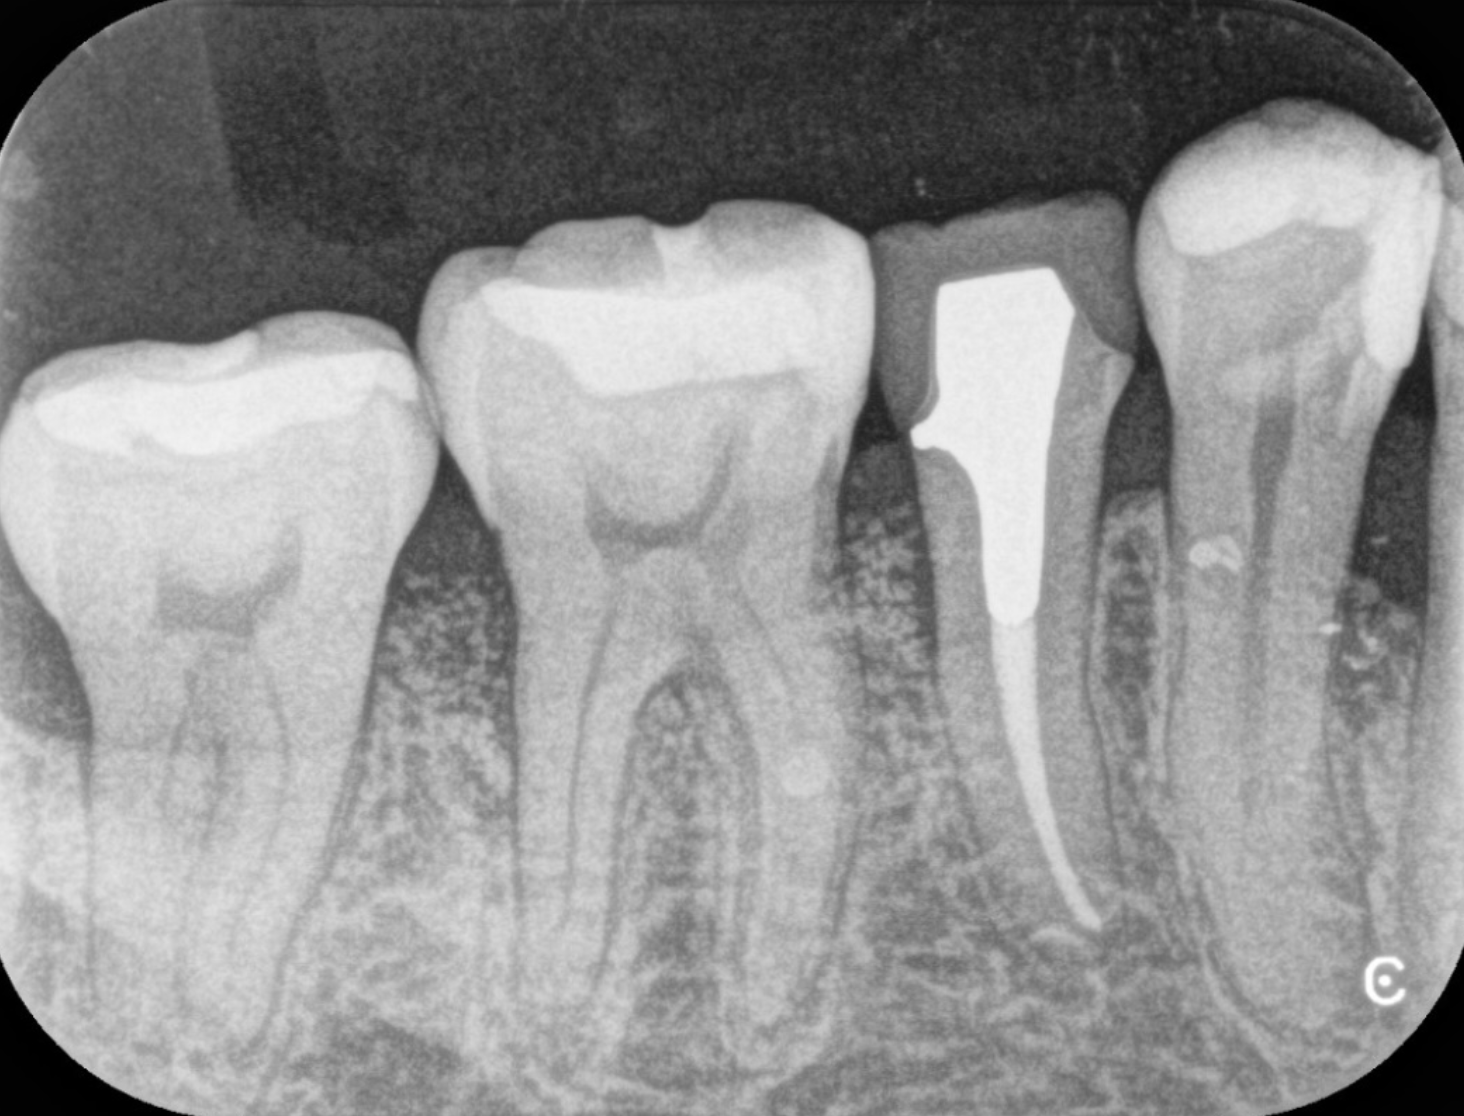

CT診断

歯周病が進行すると、歯を支える骨が溶けていきます。これを確認するために、当院では「CT」を用いたX線検査を行います。一般的に知られている「レントゲン」が二次元の画像を提供するのに対し、CTは口腔全体を三次元的に撮影するため、より詳細で立体的な映像を見ることが出来ます。